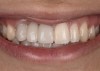

A healthy 20-year-old woman presented to the author’s office requesting treatment for a large defect in the area of missing tooth No. 7. She exhibited a high smile line that revealed a clearly visible deformity, associated with pain and sensitivity on teeth Nos. 6 and 8 and in the area of tooth No. 7 (Figure 1). Although the patient wore a modified Essix retainer, the defect was still visible because of the magnitude of tissue loss and the revealing nature of her smile.

Fig 1. The patient presented with a large deformity stemming from a congenitally missing maxillary right lateral incisor.

Figure 1